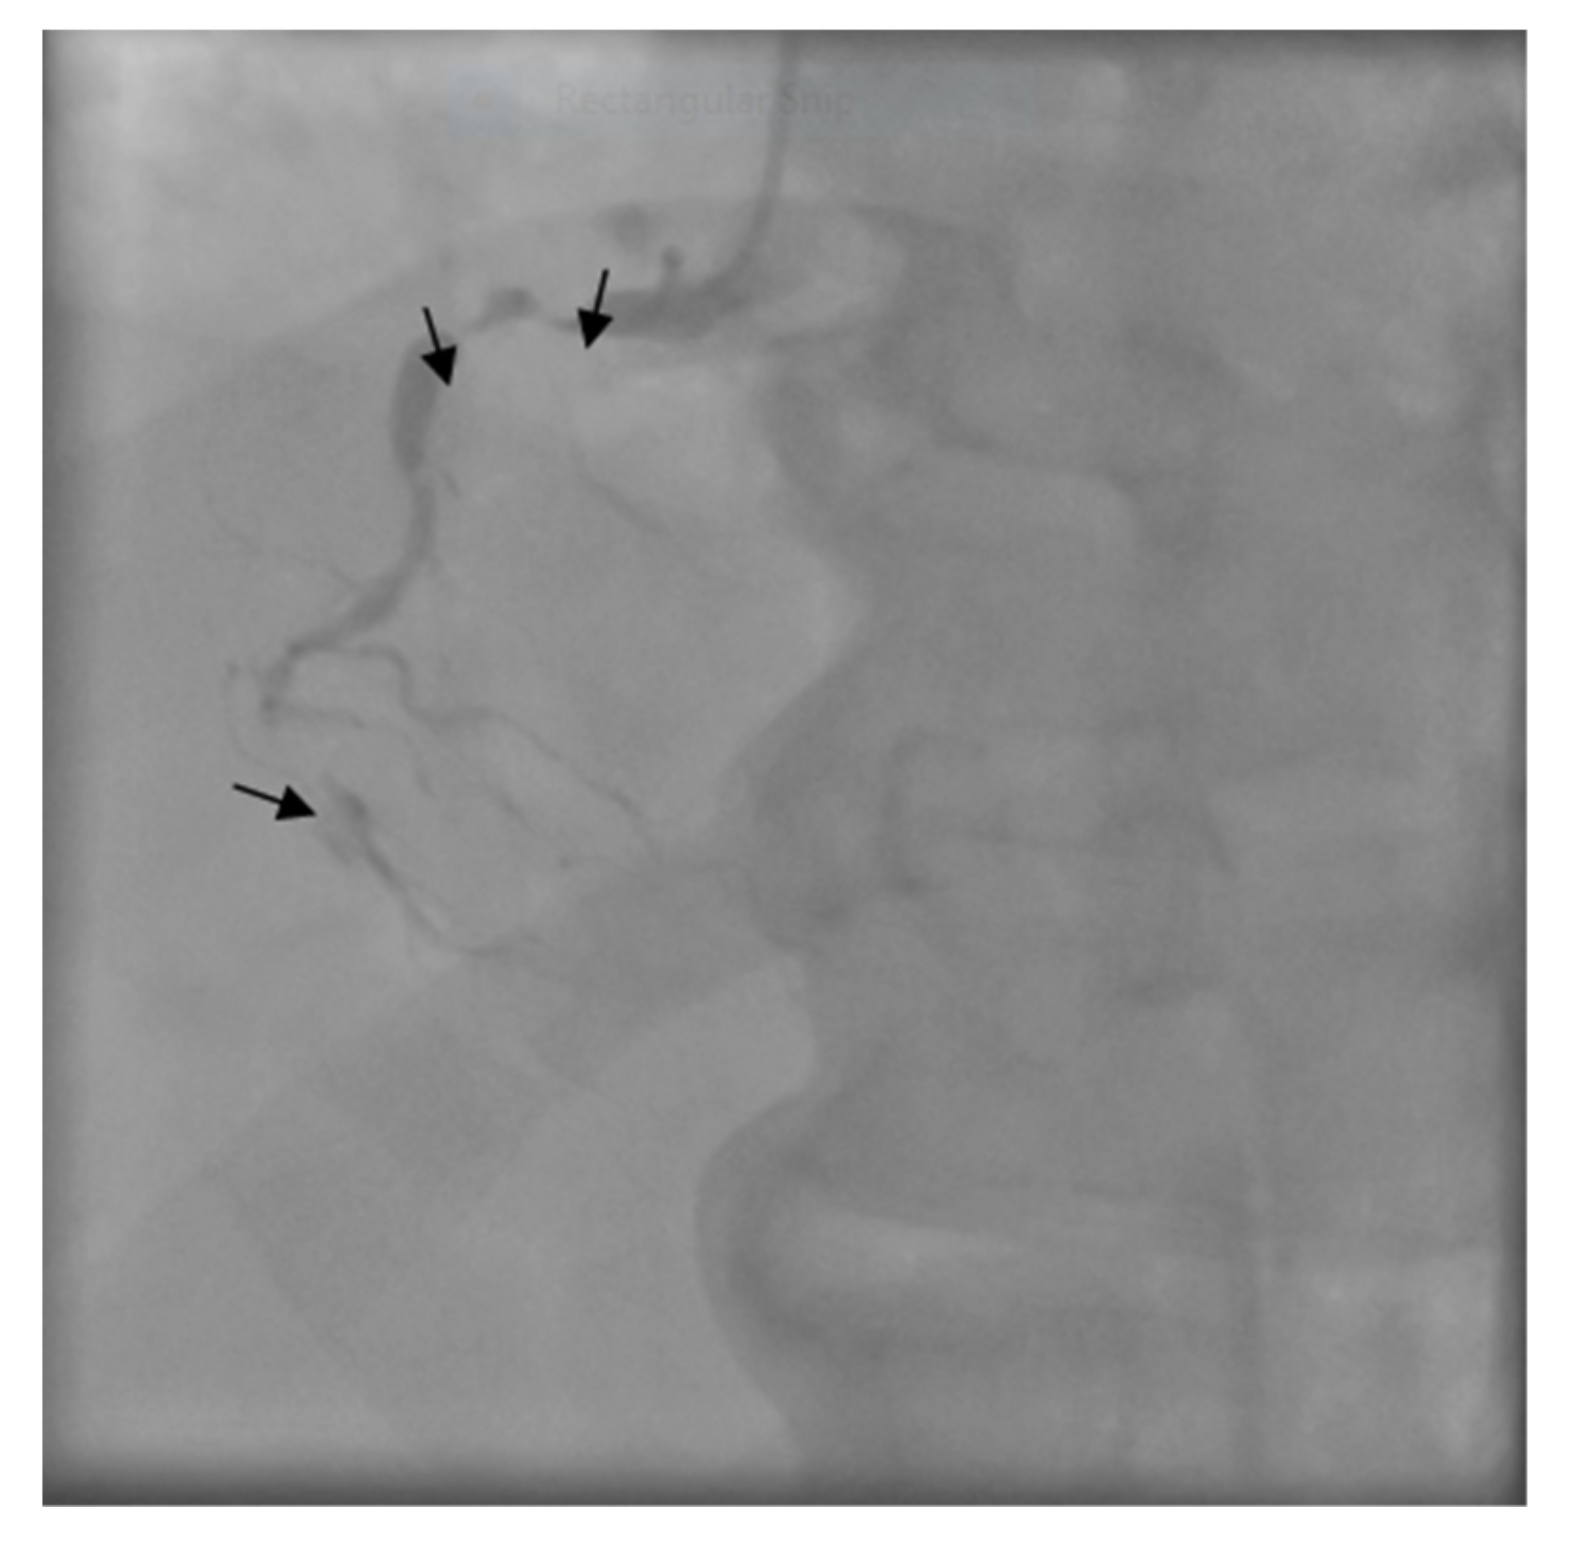

The patient was transferred to the Intensive Care Unit where he received inotropic support with Dobutamine, Levosimendan, and loop diuretics. The coronary angiogram showed a proximal critical stenosis of the left anterior descending artery (LAD) (Figure 5) and a tight lesion of the obtuse marginal (OM1) (Figure 6).

Figure 6. Right coronary angiogram - arrows show subocclusion in the second segment.